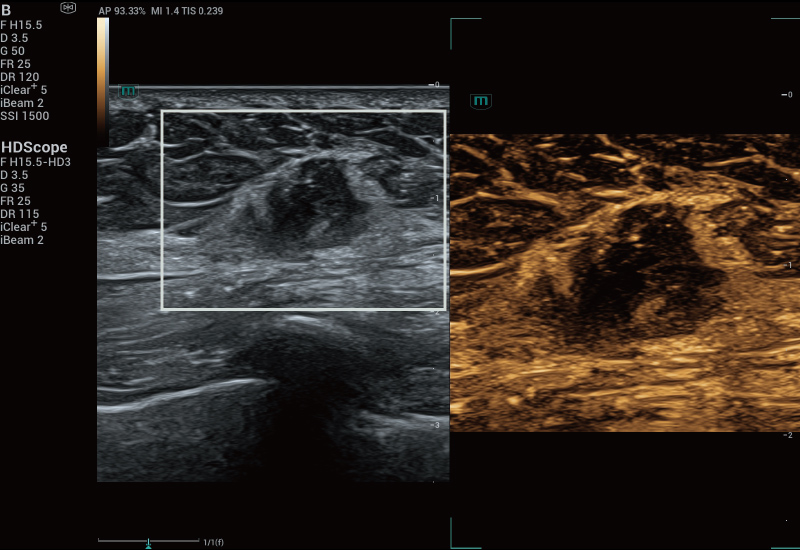

STVi maakt de kwantitatieve evaluatie van weefselviscositeit mogelijk en biedt realtime, multi-parametrische beeldvorming. Dit maakt een bredere benadering mogelijk van beeldvormingsdiagnose en kwantitatieve analyse van chronische leverziekten, borstlaesies en andere aandoeningen.

Beoordeling van borsttumoren